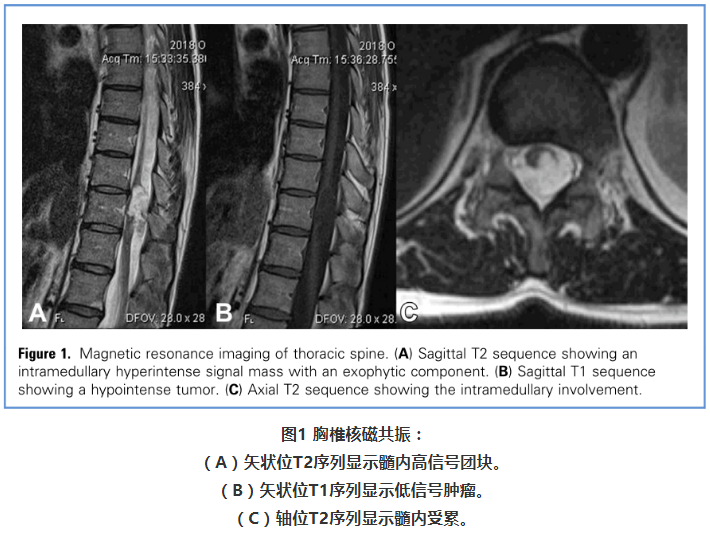

病例分享:首次手术成功切除胸段表皮样囊肿及包膜

脊髓髓内"表皮样囊肿"是什么东东?如何治疗?